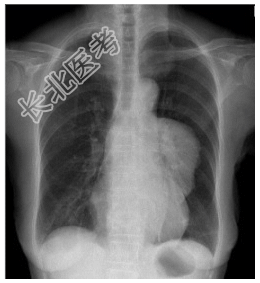

- [材料题] 患者,女性,55岁,重症肌无力多年,发现贫血1年余。查体.双侧眼睑下垂,面色苍白。行胸部平片检查。

- 简答题1、诊断及依据是什么?

- 简答题2、鉴别诊断有哪些?